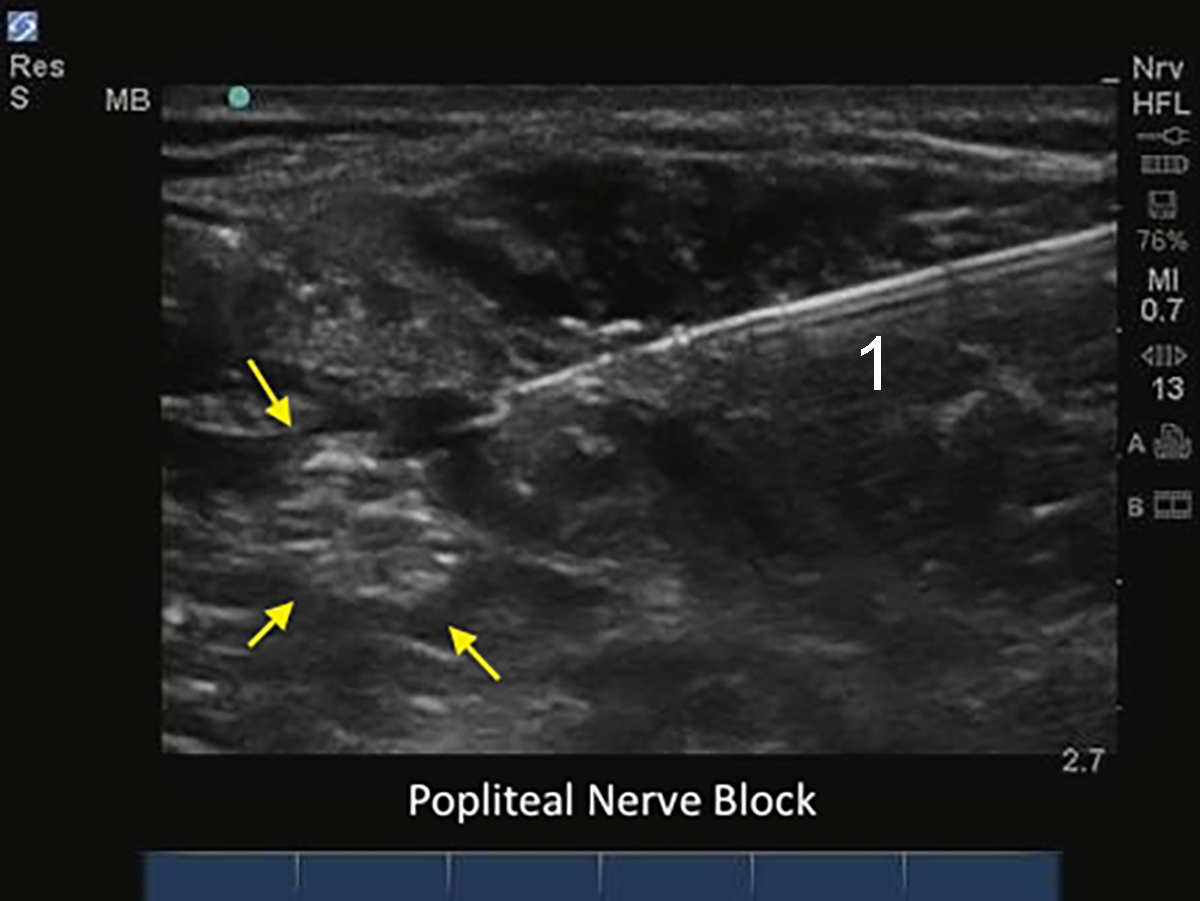

M-Turbo : Bloc du nerf sciatique poplité avec aiguille

1. Aiguille